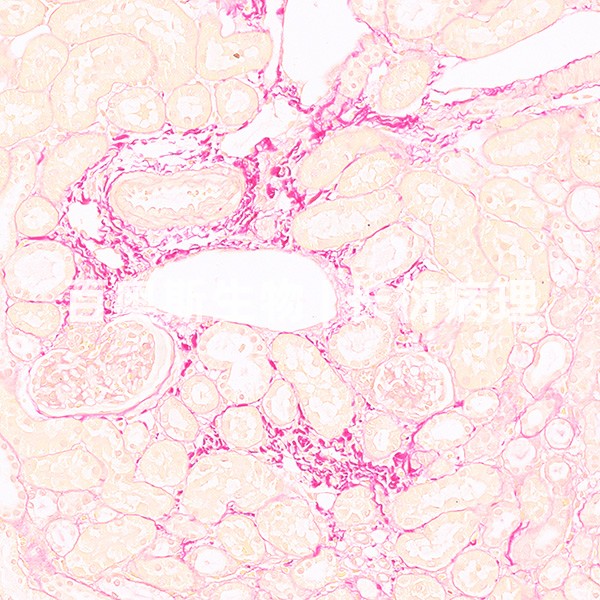

组织病理学实验

Masson染色